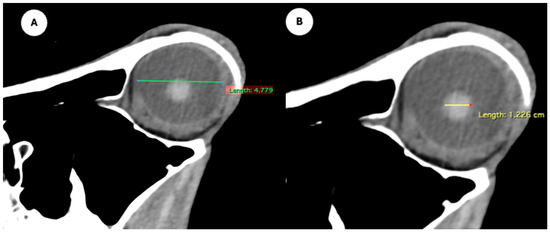

Figure 4.

Parasagittal multiplanar reconstruction (MPR) images of the equine eyeball showing (A) eyeball length and (B) the maximal antero-posterior distance of the lens measured along its midline.

- Eyeball rostrocaudal length: Maximal anteroposterior distance of the eyeball from the internal surface of the cornea to the internal surface of the choroid/retina/sclera (Figure 4A).

- Lens rostrocaudal length: Maximum anteroposterior distance of the lens measured along its midline (Figure 4B).